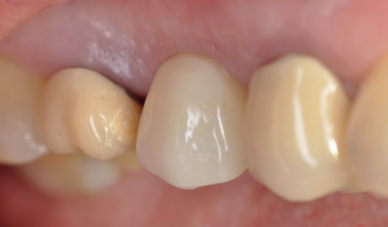

Cinco meses tras la colocación del implante, se realizó la toma de impresiones para la realización de una corona cemento-atornillada sobre una base de titanio. Un año tras la colocación de la corona, se observó el buen aspecto gingival (Figura 14) y radiográfico, donde se observa una pérdida ósea marginal fisiológica en las radiografías periapicales (Figura 15), y en los cortes del CBCT (Figura 16).